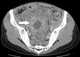

Pelvic abscess

Tubo-ovarian abscesses are one of the late complications of pelvic inflammatory disease (PID) and can be life-threatening if the abscess ruptures and results in sepsis. It consists of an encapsulated or confined 'pocket of pus' with defined boundaries that forms during an infection of a fallopian tube and ovary. [Source: Wikipedia ]